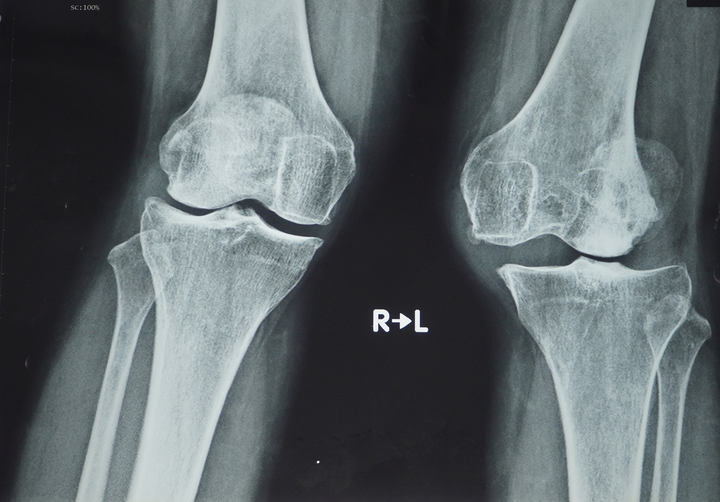

Hình ảnh khớp gối trước phẫu thuật. (Ảnh: BV Chợ Rẫy)

Bệnh nhân này bị thoái hóa khớp gối trên nền một chấn thương cũ là đứt đa dây chằng. Đây là trường hợp thay khớp gối thì đầu (đầu sụn của gối, chỗ 2 cái khớp cẳng chân), dạng bản lề lần đầu tiên được áp dụng thành công tại Việt Nam.

Cách đây 3 năm, sau một vụ tai nạn, chị C. bị trật khớp gối, tổn thương đa dây chằng. Bệnh nhân sau đó trải qua quá trình điều trị kéo dài ở nhiều bệnh viện khác nhau nhưng vẫn chưa tìm ra phương pháp điều trị thích hợp.

Để chuẩn bị cho ca phẫu thuật, ê-kip bác sĩ đã sử dụng nhiều hình ảnh chụp chiếu khác nhau nhằm dựng hình toàn bộ khớp gối. Các hình ảnh và thông tin sau đó được gửi đến cho đối tác tại Đức để chọn một khớp gối bằng titanium vừa vặn kích thước với khớp gối của bệnh nhân C.